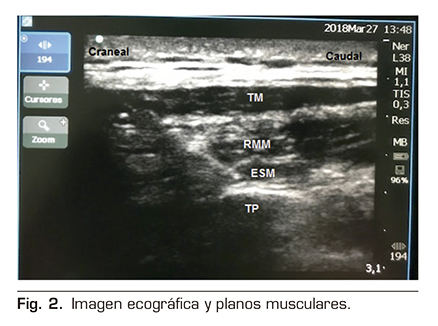

Se le realizó un bloqueo ecoguiado ESPB con colocación de catéter para analgesia continua posterior. Para ello, se colocó al paciente en posición de decúbito lateral derecho, y se procedió a la preparación de la zona de punción con povidona yodada, colocación de campo estéril y elección de sonda ecográfica lineal de alta frecuencia. Se identificó la apófisis espinosa de la 6.ª vértebra torácica y a una distancia de 3 cm lateral se identificó el proceso transverso de la misma. En la imagen ecográfica, visualizamos el plano subcutáneo y varios grupos musculares que de superficial a profundo corresponden con el músculo trapecio, romboides y erector de la columna, todos ellos sobre la apófisis transversa vertebral (Figura 2).